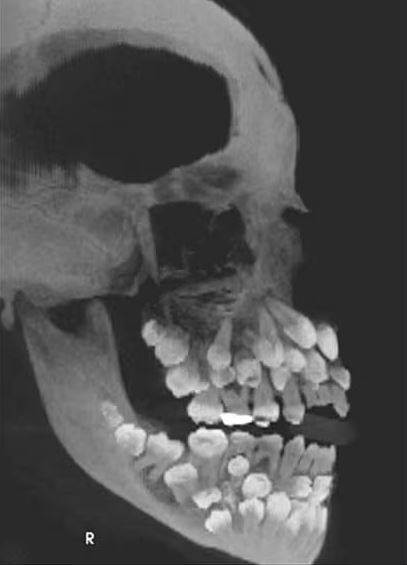

根據媒體《Chosun Biz》的報導,《美國齒顎矯正與顏面矯形學期刊》2011年曾刊登一起罕見病例,巴西一名11歲女童因想拔除一顆上排乳牙就醫,起初牙醫進行口腔檢查時並無異狀,誰知在照完X光後醫生大驚失色,因為女童嘴裡竟藏了18顆乳牙、32顆恆牙,以及31顆多生牙,一張小嘴共擁有多達81顆牙齒。

據了解,一般成人的正常牙齒數量為32顆,額外長出的牙齒被稱為「多生牙」,通常多生牙數量不會超過2顆。但女童足足有超過30顆多生牙,情況實屬罕見,醫療團隊進一步為女童做遺傳檢測,這才發現她第9對染色體中出現「染色體倒位」的異常結構,也就是部分染色體片段呈現反轉,或許就是造成她多生牙爆量的原因。

多生牙有的會深埋在牙齦內,有的外觀也與正常牙齒無異,雖然靠肉眼無法察覺,但很可能會阻礙正常牙齒生長或牙齒排列混亂,甚至引發囊腫等其他併發癥,貿然拔除還可能損傷顎骨。醫療團隊因此集結了牙周、矯正、口腔外科、贋復等專家,為女童訂定長期治療計畫,盼能安全處理這些多出來的牙齒。